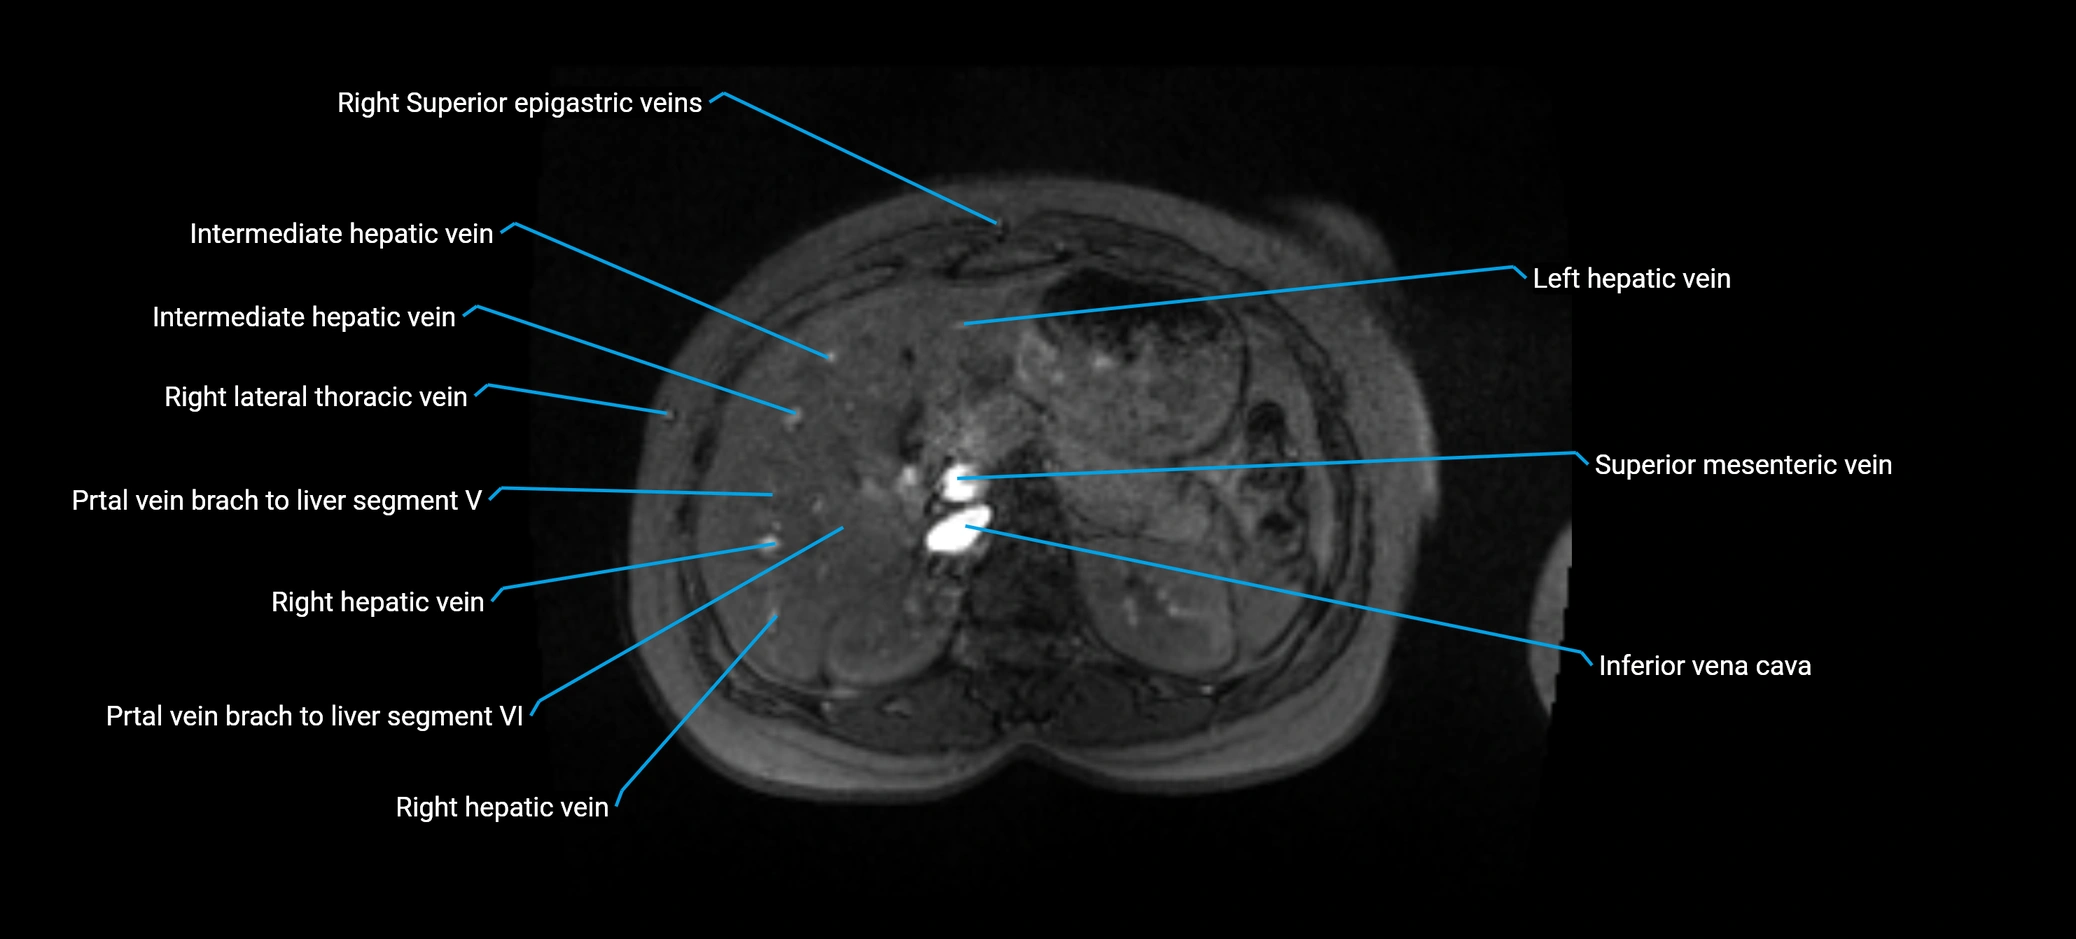

The anterior right branch of the portal vein is a major intrahepatic division of the right portal vein. After the main portal vein bifurcates into right and left branches, the right portal vein divides into anterior and posterior segmental branches.

The anterior right branch supplies the anterolateral liver segments (Segment V) and anteromedial liver segments (Segment VIII) within the right hepatic lobe. It operates as a key vascular route delivering nutrient-rich portal venous blood to the central and superior right liver.

• Segment V (anteroinferior right lobe)

• Segment VIII (anterosuperior right lobe)

MRV TOF (Time-of-Flight MR Venography):

• Appears as a bright, high-signal vascular channel representing flowing blood

• Clearly shows branching pattern of right portal vein into anterior and posterior branches

• Best in coronal or axial reconstructions for segmental mapping

• Enhances brightly and homogeneously during the portal venous phase

• Clearly delineates branching into segments V and VIII

• Best sequence for evaluating patency, caliber, and anatomic variants

MRI image

image